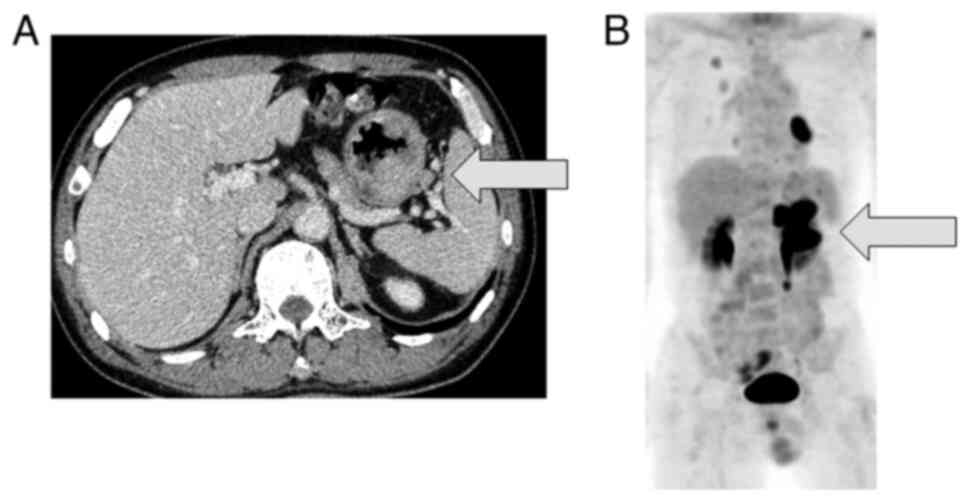

Figure 9

(A) Computed tomography scan showing a protruding mass in the upper part of the stomach (arrow). (B) FDG-positron emission tomography showing FDG uptake in the stomach (arrow), and pericardial metastasis (Case 2).

A 64-year-old man was referred to Mie University hospital on October, 2011 due to a mass on the posterior aspect of the left proximal leg. The patient had a history of a Billroth I gastroduodenostomy for a peptic ulcer. A radiograph showed an osteolytic lesion in the left proximal fibula. MRI of the left knee revealed a 6 cm mass around the proximal left fibula (Fig. 6). CT of the head, chest, abdomen, and pelvis did not demonstrate any distant metastases. An incisional biopsy was performed. Histological analysis revealed remarkably polymorphous spindle cell proliferation. Immunohistochemically, the tumor was positive for α-smooth muscle actin, desmin, and caldesmon, but negative for S100, C56, and pan CK (Table I). The aforementioned morphological and immunohistochemical findings were consistent with LMS (Figs. 7A and B, and 8). Neoadjuvant chemotherapy using doxorubicin and ifosfamide was administered. However, the lower leg could not be salvaged due to the diffuse spread to the tibia and popliteal artery. Thus, an above-knee amputation was performed. A total of 2 months after surgery, he developed multiple lung metastases. RFA was performed regularly for the lung metastases. After 1 year, the patient developed a bone metastasis of the left femur, and cryoablation and internal fixation, using a compression hip screw were performed. After 2 years, the patient presented with severe anemia without any gastrointestinal manifestations. CT revealed a protruding mass in the upper part of the stomach (Fig. 9A), and a large pericardial mass with a diameter of 56 mm. Intense FDG uptake in the stomach, left diaphragm, pericardial mass, and paraspinal muscles at the L1 and L4 levels were observed on FDG-Positron emission tomography (Fig. 9B). Cryoablation was performed for the diaphragm metastasis and paraspinal muscle metastasis. Endoscopy revealed a protruding lesion in the anastomotic site of the Billroth I, which was spreading to the jejunum (Fig. 10). The patient underwent combined resection of the stomach and transverse colon. Subsequent histochemical staining confirmed the diagnosis of gastric metastasis from LMS (Fig. 7C).